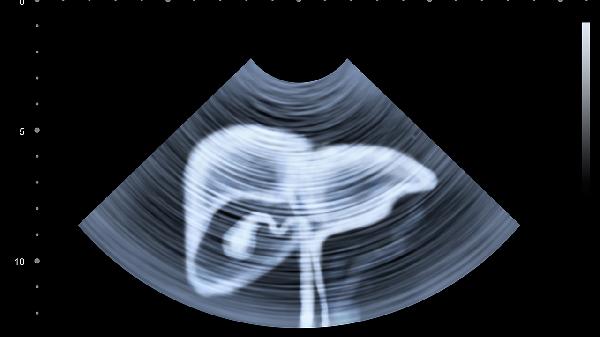

2、肝脏:

肝脏作为人体最大实质性器官,位于右季肋区,体积大且位置表浅。外力作用可能导致肝包膜下血肿或肝实质破裂,常伴有右上腹压痛、腹膜刺激征等表现。肝脏损伤的处理需根据损伤程度选择观察、介入栓塞或手术治疗。